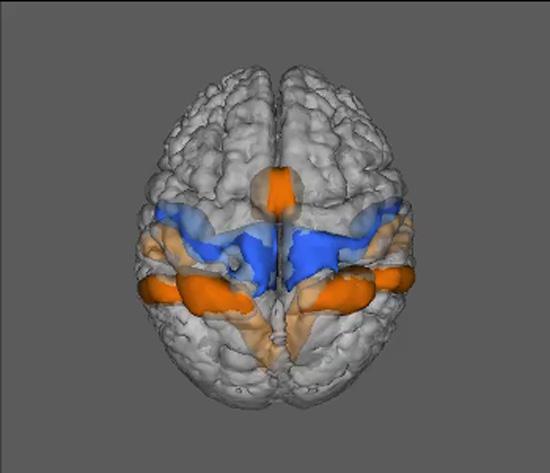

An illustration of a brain

Musculoskeletal disorders affect more than one out of every two persons in the United States age 18 and over, and nearly three out of four age 65 and over. Low back pain (LBP) in particular exerts a staggering burden. For more nearly 20 years we have conducted research determining the effectiveness of conservative treatments, such as manual therapies and exercise, to minimize pain and disability associated with musculoskeletal pain and injury. In addition, this work has sought to elucidate the physiological effects and consequences of these treatments.